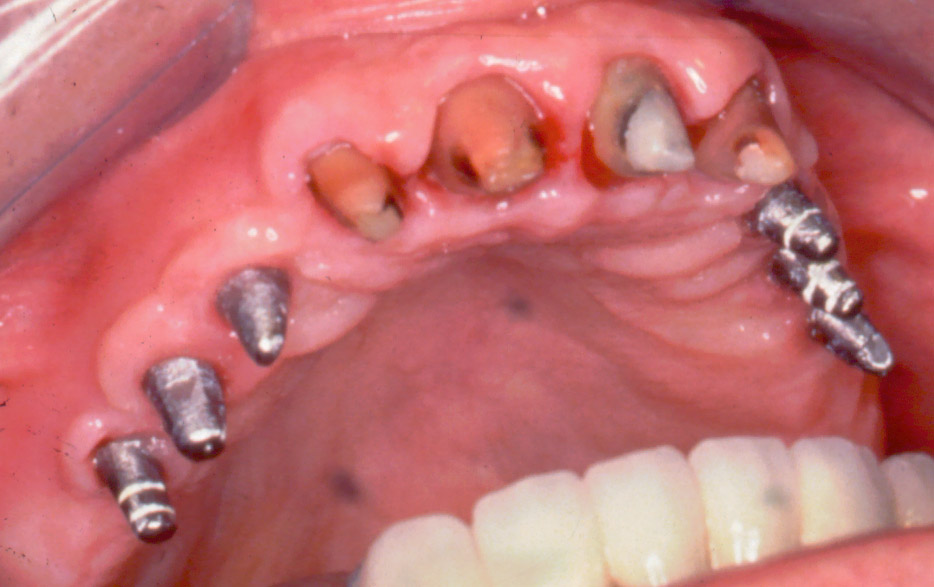

El paciente no presenta incidencias hasta el año 2005, cuando acude a consulta con el segmento distal derecho desprendido y en el que se había producido una fractura de los aditamentos macizos a nivel de la unión del aditamento con implante, de forma que la rosca fracturada del aditamento está encajada dentro de los implantes.

El tratamiento que se intento fue extraer las roscas rotas con ultrasonidos, pero no se pudo, por lo que procedimos a realizar el vaciado de estas roscas rotas y a realizar unas espiras nuevas en estos vaciados con un set de machos roscantes, para después roscar nuevos aditamentos originales de la casa ya fabricados en aleación de titanio (grado V) . Una vez instalados los aditamentos procedimos a su tallado y a realizar la prótesis ceramo–metálica como tenía antiguamente.